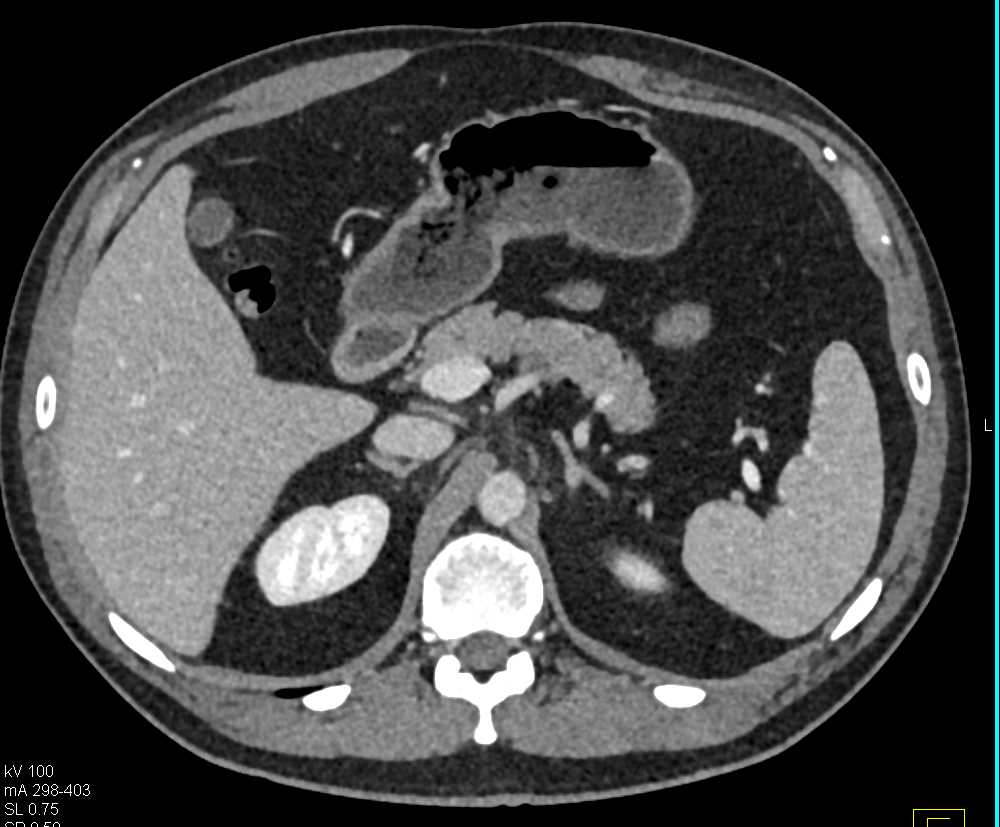

Neuroendocrine Tumor Body of Pancreas